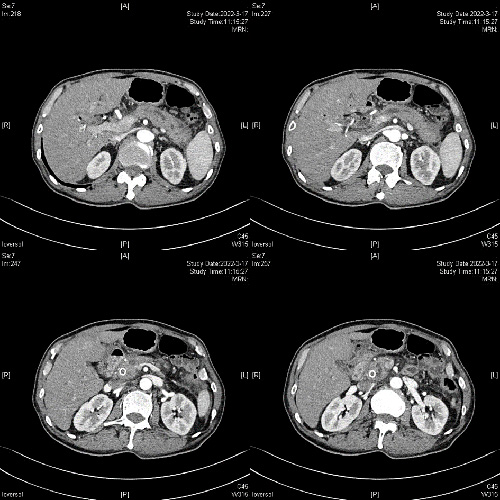

患者摆好手术体位后,胡锦华主任医师及科室医护人员在崔屹主任医师指导下,在超声内镜下精准穿刺主胰管,造影证实主胰管明显扩张(约5mm),导丝反复探查并越过胰头部病变经十二指肠乳头进入肠道。更换十二指肠镜后捕获导丝并由活检通道取出,再按经典ERCP操作,扩张狭窄段,置入支架,手术顺利完成。术后第2天,老孙自觉疼痛缓解,胰腺淀粉酶指标降至正常。